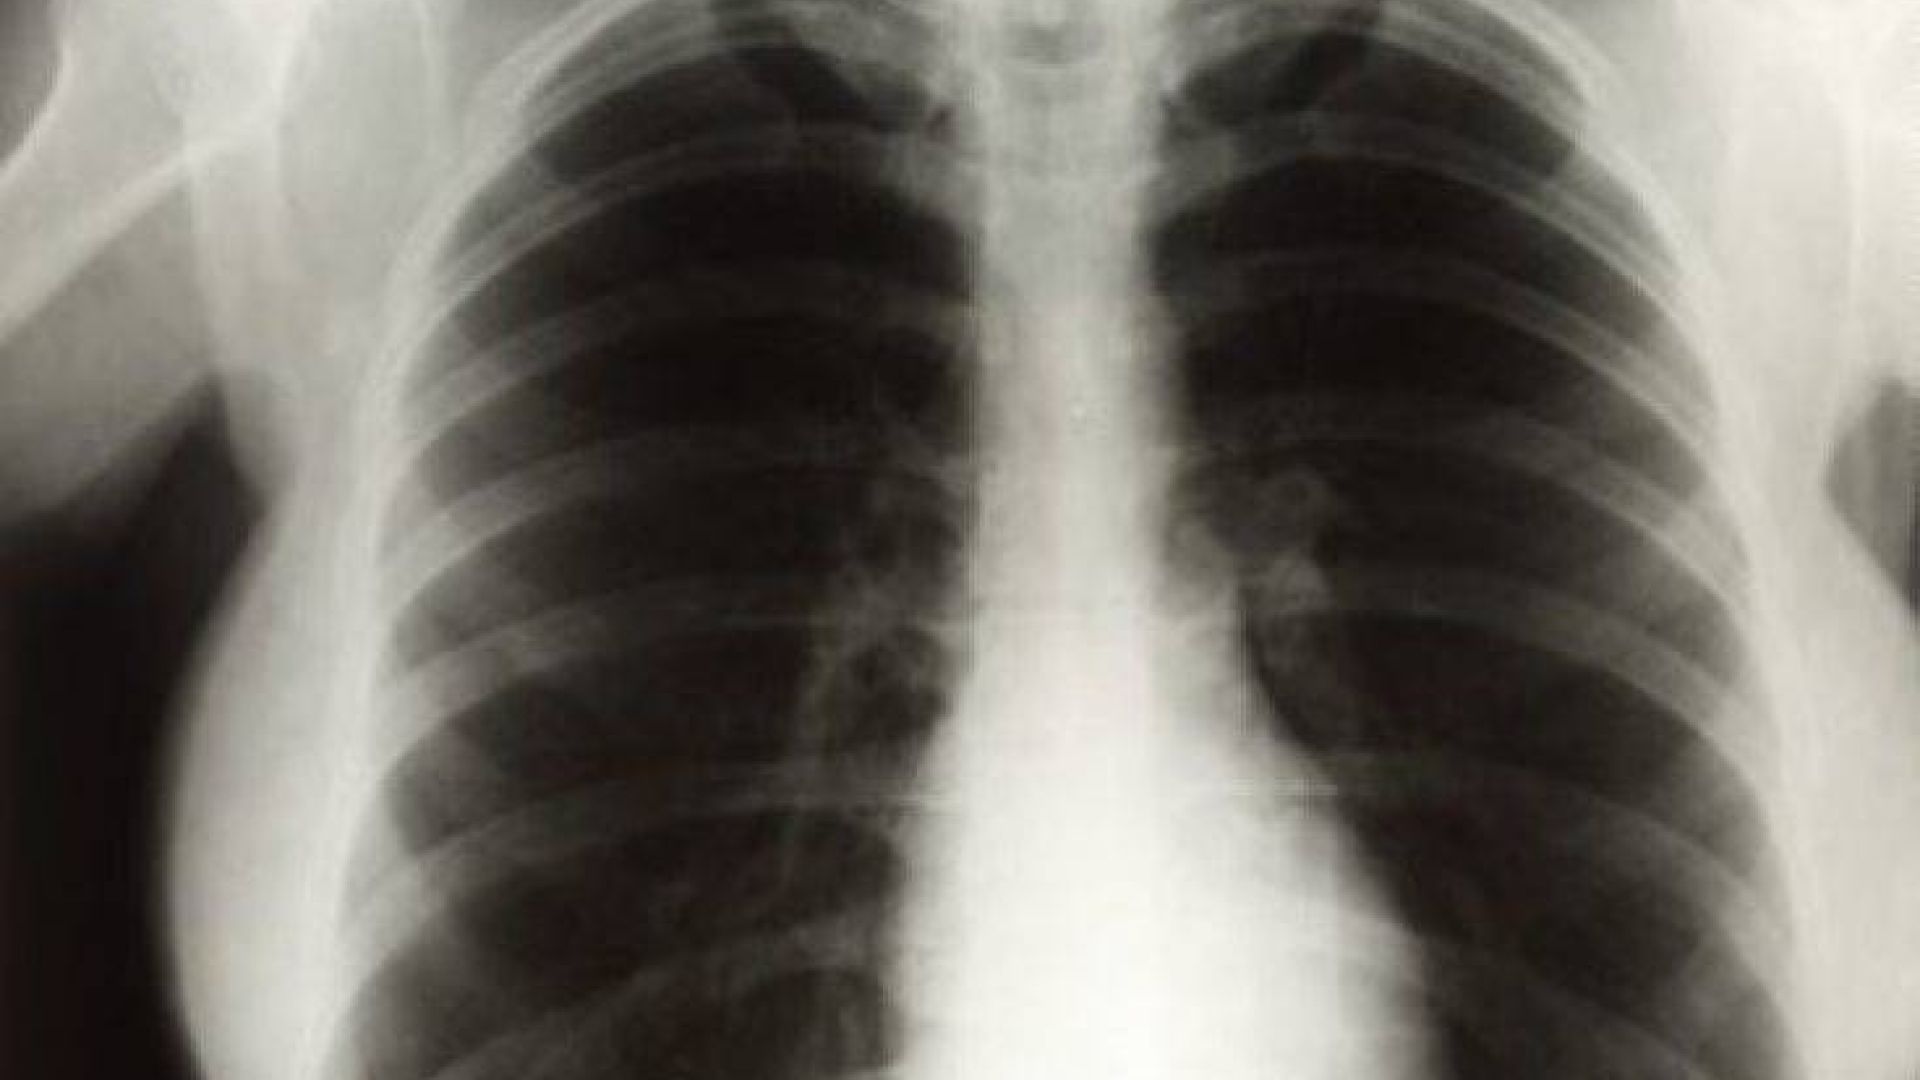

Ένα νέο σύστημα τεχνητής νοημοσύνης της Google Health, θυγατρικής της Google στο πεδίο της «έξυπνης» υγείας, μπορεί να μελετήσει ακτινογραφίες πνευμόνων και να βγάλει συμπεράσματα εξίσου αξιόπιστα με εκείνα των έμπειρων ακτινολόγων. Το σύστημα βαθιάς μάθησης της Google, σύμφωνα με τους δημιουργούς του, μπορεί να αποτελέσει πολύτιμο βοηθό των γιατρών στο μέλλον.

Οι ερευνητές, που έκαναν τη σχετική δημοσίευση στο περιοδικό «Radiology» της Ακτινολογικής Εταιρείας της Βόρειας Αμερικής, εκπαίδευσαν το σύστημά τους τροφοδοτώντας το με περισσότερες από 860.000 ακτινογραφίες. Η ακτινογραφία πνευμόνων είναι από τις συχνότερες εξετάσεις παγκοσμίως, όμως έχει ορισμένους περιορισμούς.

Οι δοκιμές του συστήματος από επιτροπή ακτινολόγων έδειξαν ότι τα καταφέρνει τουλάχιστον εξίσου καλά με τους γιατρούς στην ανίχνευση διαφόρων προβλημάτων (διάγνωση καταγμάτων, οζιδίων, όγκων, πνευμοθώρακα κ.ά.).